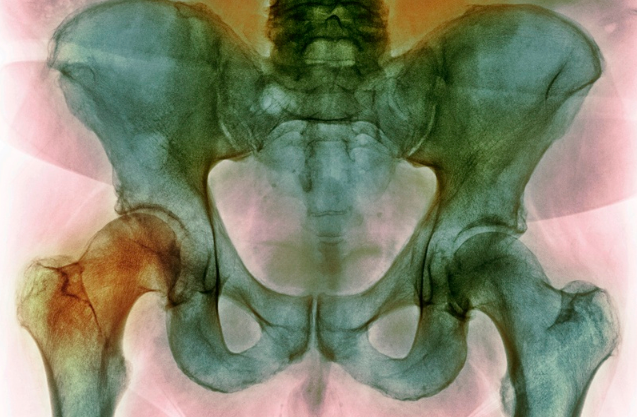

골반 틀어짐

출산 후 골반통이 지속됨이런 증상이 있다면?

허리, 무릎, 다리 통증

다리 길이 차이나 체형 불균형

골반 틀어짐은 체형 불균형의 핵심 요인 중 하나입니다.

장시간 잘못된 자세, 다리 길이 차이, 척추측만, 심지어는 출산 후 골반이 벌어지면서 발생하기도 해요.

이런 틀어짐은 고관절, 척추, 무릎까지 영향을 줄 수 있습니다.

어떤 치료가 효과적일까요?

운동치료로 약화된 근육 강화

도수치료로 긴장된 근육 이완

추나요법으로 골반 관절 교정

약침치료로 통증 완화 및 기능 강화

골반 틀어짐은 방치하면 만성 통증으로 이어질 수 있으니, 조기 검진이 중요합니다.